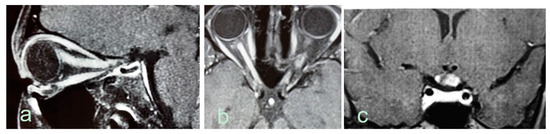

2.6. Magnetic Resonance Imaging